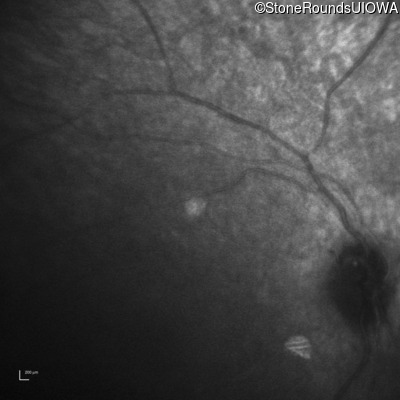

Infrared Fundus Photograph - Right -

No Light Perception

Infrared Fundus Photograph - Left -